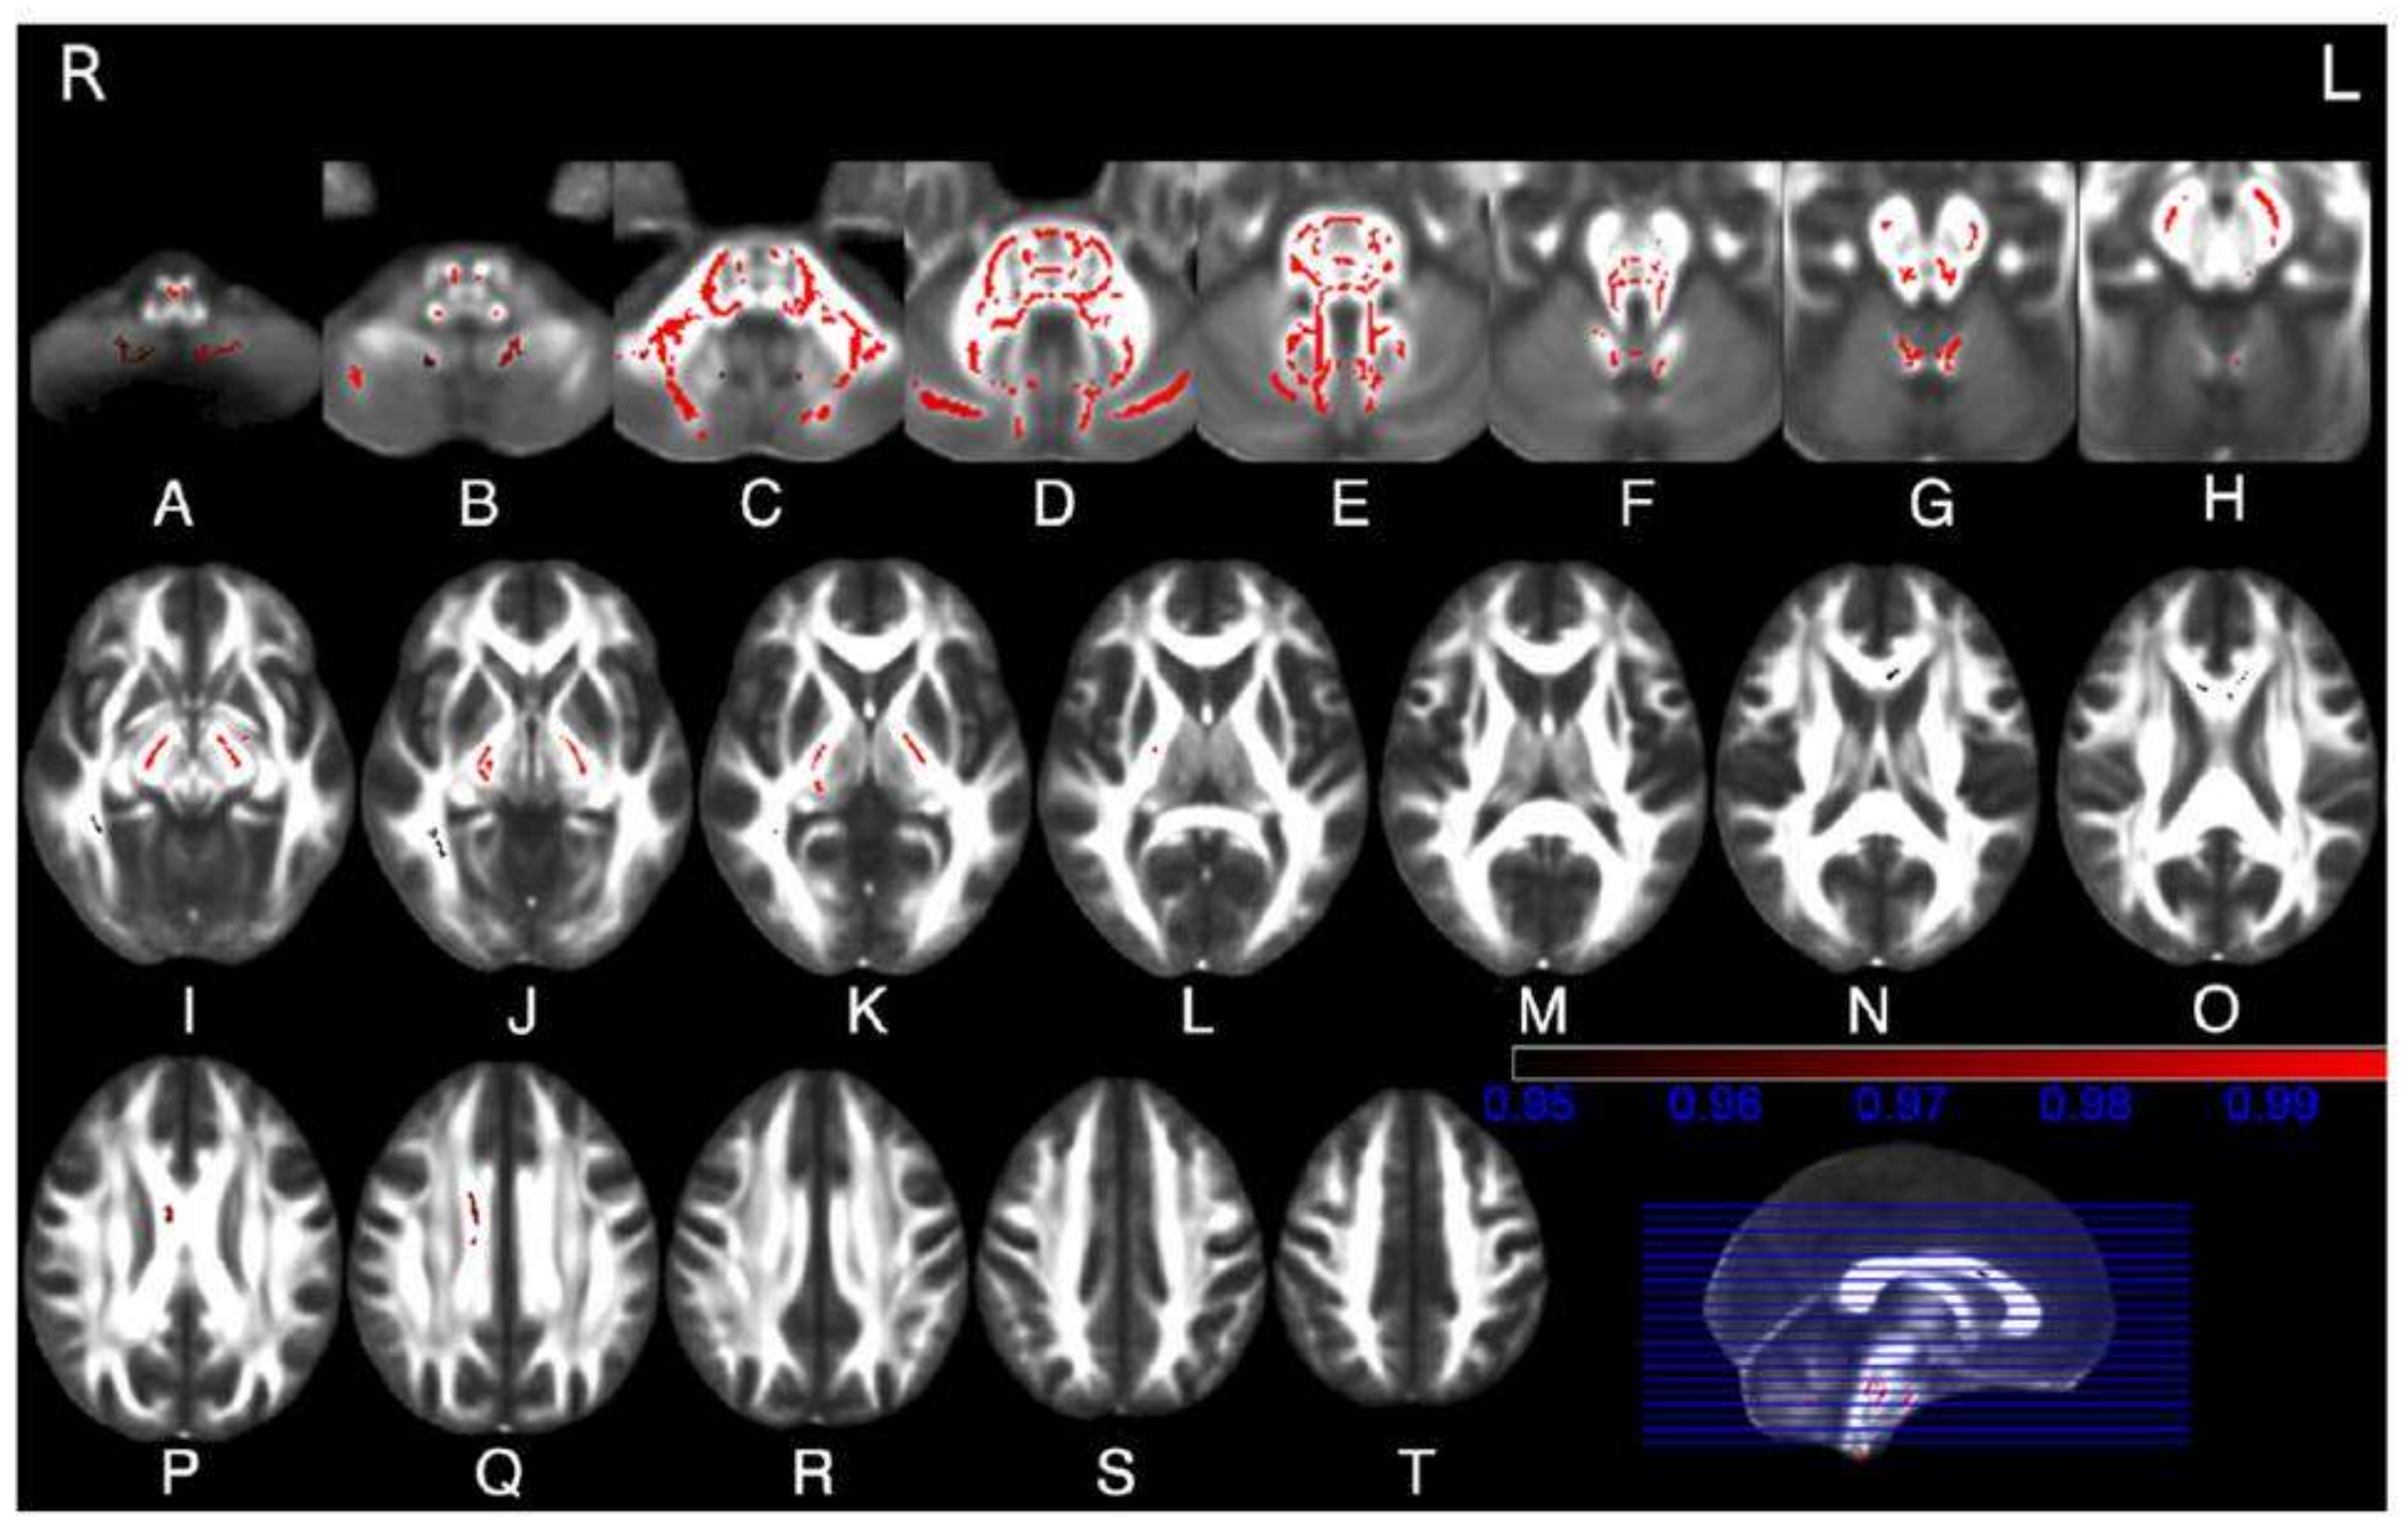

- Mascalchi, M.; Diciotti, S.; Giannelli, M.; Ginestroni, A.; Soricelli, A.; Nicolai, E.; Aiello, M.; Tessa, C.; Galli, L.; Dotti, M.T.; et al. Progression of brain atrophy in SCA2. A longitudinal TBM study. PLoS ONE 2014, 9, e89410. [Google Scholar] [CrossRef] [PubMed]

- Mascalchi, M.; Marzi, C.; Giannelli, M.; Ciulli, S.; Bianchi, A.; Ginestroni, A.; Tessa, C.; Nicolai, E.; Aiello, M.; Salvatore, E.; et al. Histogram analysis of DTI-derived indices reveals pontocerebellar degeneration and its progression in SCA2. PLoS ONE 2018, 13, e0200258. [Google Scholar] [CrossRef]